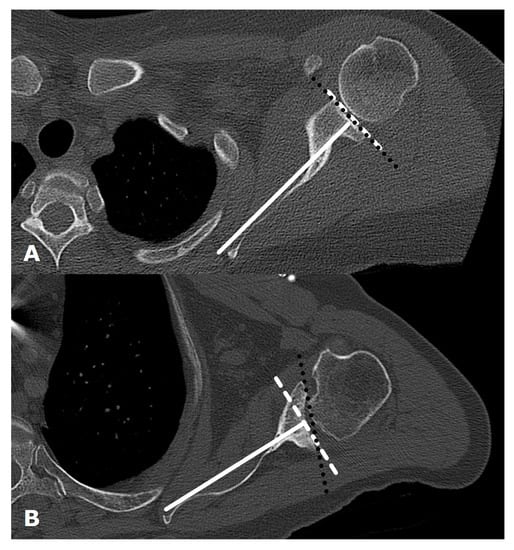

3. Preoperative Imaging

5.1.1. Humeral Head Resurfacing/Stemless Hemiarthroplasty (HHRA)